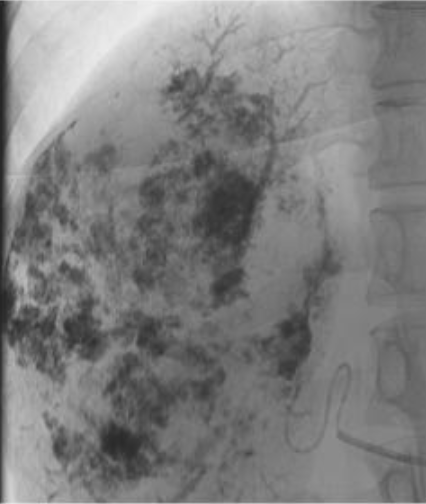

The tumor then shrinks over time , will complete resolution of symptoms.

One year follow up below , 90 % shrinked , the rest will shrink with time , and we lose nothing giving it time to completely shrink , all symptoms (pain in this case) resolved after treatment (embolisation ).

Liver hemangiomas causing symptoms can be treated , you do not need a biopsy to confirm that it is a hemangioma.